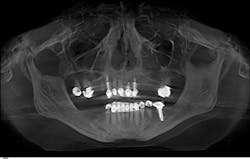

Let's take a closer look at the patient here to illustrate my point.

For most of us, this is a typical patient who walks into our offices. A clinical exam reveals recurrent decay around several existing crowns, mobility of the upper and lower anterior teeth, and generalized bone loss. In this case, my patient and I agree that saving the remaining teeth, which is certainly possible, would require extensive dentistry and would have a guarded prognosis. She has accepted the fact that she will lose all of her teeth. However, after talking with other people, she is adamant that she must have implants on the lower arch for improved retention.

So, our final treatment plan looks like this:

- Extract teeth Nos. 1, 2, 6, 7, 8, 9, 10, 15, 20, 21, 22, 23, 24, 25, 26, 27, 28 (17 teeth) and alveoplasty

- Immediate healing denture upper and lower

- Implant placement site Nos. 22 and 27

- Final upper esthetic denture

- Final lower overdenture with locator abutments